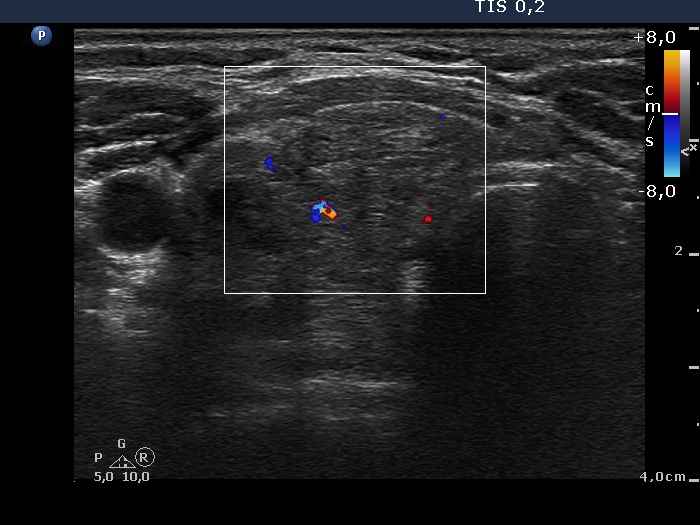

Discrete lesion or nodule in Hashimoto's thyroiditis - case 14 (377) (ultrasonographic picture 4)

Right lobe, longitudinal scan

Right lobe, transverse view, color Doppler mode. The vascularization is scanty.